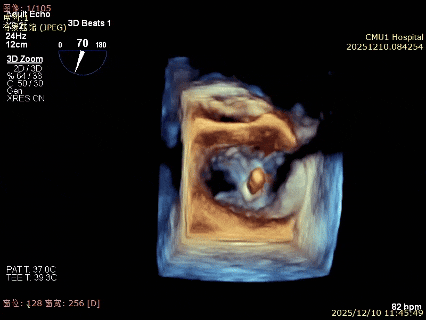

术前3D

术前3Dcolor

3D-TEE二尖瓣相关解剖学参数:后叶长度:22-25mm,前叶长度:31-34mm;瓣环AP径:47mm,ML径:48mm;瓣口面积:约7.8cm²;脱垂宽度:30mm,最大连枷间距:14mm。

术前即刻TEE进一步明确了二尖瓣反流的机制(DMR)及反流程度(5+),重点完善了病变区域二尖瓣解剖结构的评估,预估手术难点/影响手术效果的解剖结构为冗长的二尖瓣后叶(PML约25mm),宽大的脱垂(Flail Width约30mm),超大的连枷间距(Flail gap约14mm)。